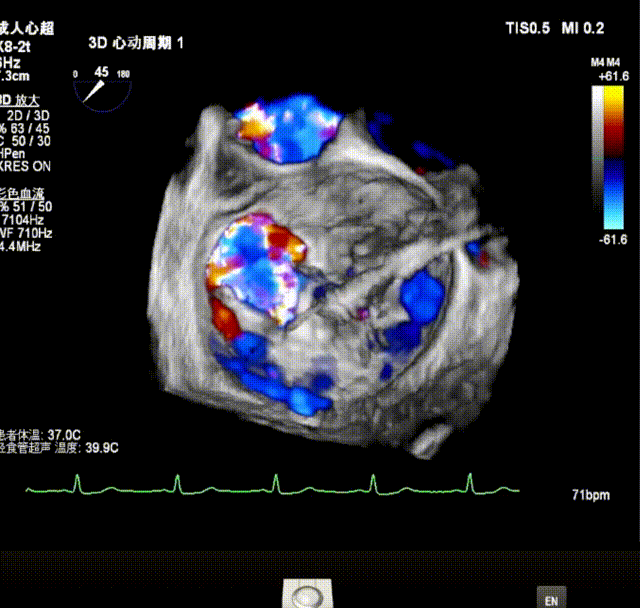

瓣膜夹释放前评估发现返流改善明显,仅存少量返流。

最终释放用多普勒超声评估返流程度,返流情况改善明显,仅存在极微小返流;无瓣口狭窄;肺静脉逆流情况消失,血流动力学显著改善;3D超声下,瓣膜组织桥稳定。术后即刻评估,术后反流消失(MR 0+),术后跨瓣压差2mmHg,手术成功。

X-plane视窗可见二尖瓣2区脱垂;3D enface view示二尖瓣内P2脱垂,偏心性返流

最终释放用多普勒超声评估返流程度,返流情况有效改善,术后仅残留少量反流( MR 1+),术后跨瓣压差3mmHg;无瓣口狭窄;肺静脉逆流情况消失,血流动力学显著改善;3D超声下,瓣膜组织桥稳定。术后即刻评估,返流有效降低至少量(1+),手术成功。